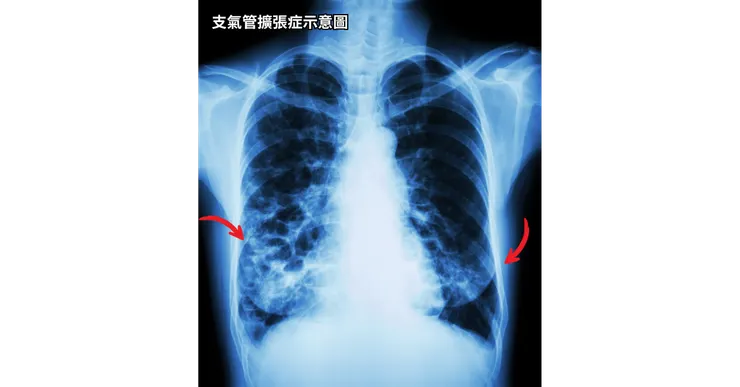

十四.支氣管擴張症

支氣管擴張症Wen Lung解釋,其實就是像它的字面上的意思,它是結構上面的問題,就是你的支氣管平常都是固定的寬度,可能從上到下越來越窄,但是如果你有支氣管擴張症的問題,你的細支氣管又是比較末端的這些支氣管,它是被撐開來的結構變化的關係,所以它比較容易感染、積痰,也會因爲這樣你會想要把痰咳出來,就是比較多咳嗽的狀況。